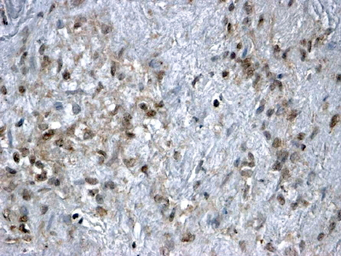

IHC-P analysis of paraffin embedded human ovary using GTX25096 FOXL2 antibody, C-term.

Antigen retrieval : Steamed antigen retrieval with citrate buffer pH 6

Dilution : 2μg/ml